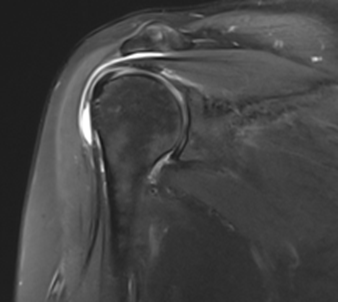

그림3.png 촬영 일시: 2025.07.02

<Fig 1. 회전근개의 부분파열 및 근위축소견>

1️⃣ 퇴행성 목디스크 - 목 신경을 압박하고 있었음

2️⃣ 회전근개 부분파열 - 어깨 힘줄이 찢어진 상태

3️⃣ 팔신경 손상 - 신경 자체가 손상되어 근위축까지 진행